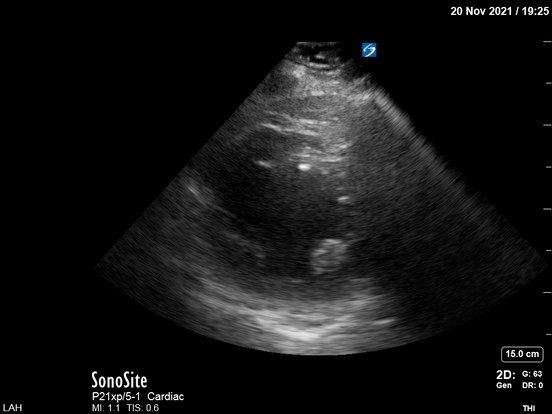

Very difficult 4-chamber view showing an unhappy LV:

Sometimes it's impossible to get good views. Even with US enhancing agent (Definity), Cards could not (later) get a nice view (but ruled out apical clot):